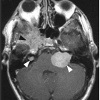

МРТ мосто-мозжечковых углов

Магнитный резонанс мозговых углов мозжечка. Целевая визуализация области закрытия трех структур мозга - моста, мозгового вещества и мозжечка при воздействии на область, исследуемую электромагнитными волнами в постоянном магнитном поле. Основными показаниями для данного исследования являются признаки повреждения V-VIII пар черепных нервов (нейросенсорная глухота, головокружение, паралич лицевых мышц, онемение кожи лица ). Причинами этих нарушений могут стать опухоли (невромы, шванномы и ), Эпидермоидные и паутинные кисты, аневризмы церебрально-мозжечкового угла. МРТ коры головного мозга с улучшенным контрастом позволяет не только выявить причину патологических симптомов, но и определить точное местоположение и распространенность опухолей, что крайне важно для планирования хирургического вмешательства.